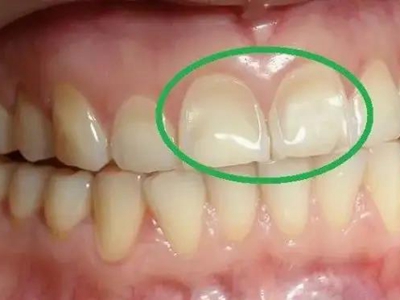

酸蚀症前牙面出现浅沟凹陷小坑图

酸蚀症患者的单个牙齿前面靠近牙龈处出现浅沟凹陷,表面有小坑,颜色与正常牙齿相比明显发黄,用手指触摸表面时会感到凹凸不平,牙齿较为敏感,易受到冷、酸等外界刺激。